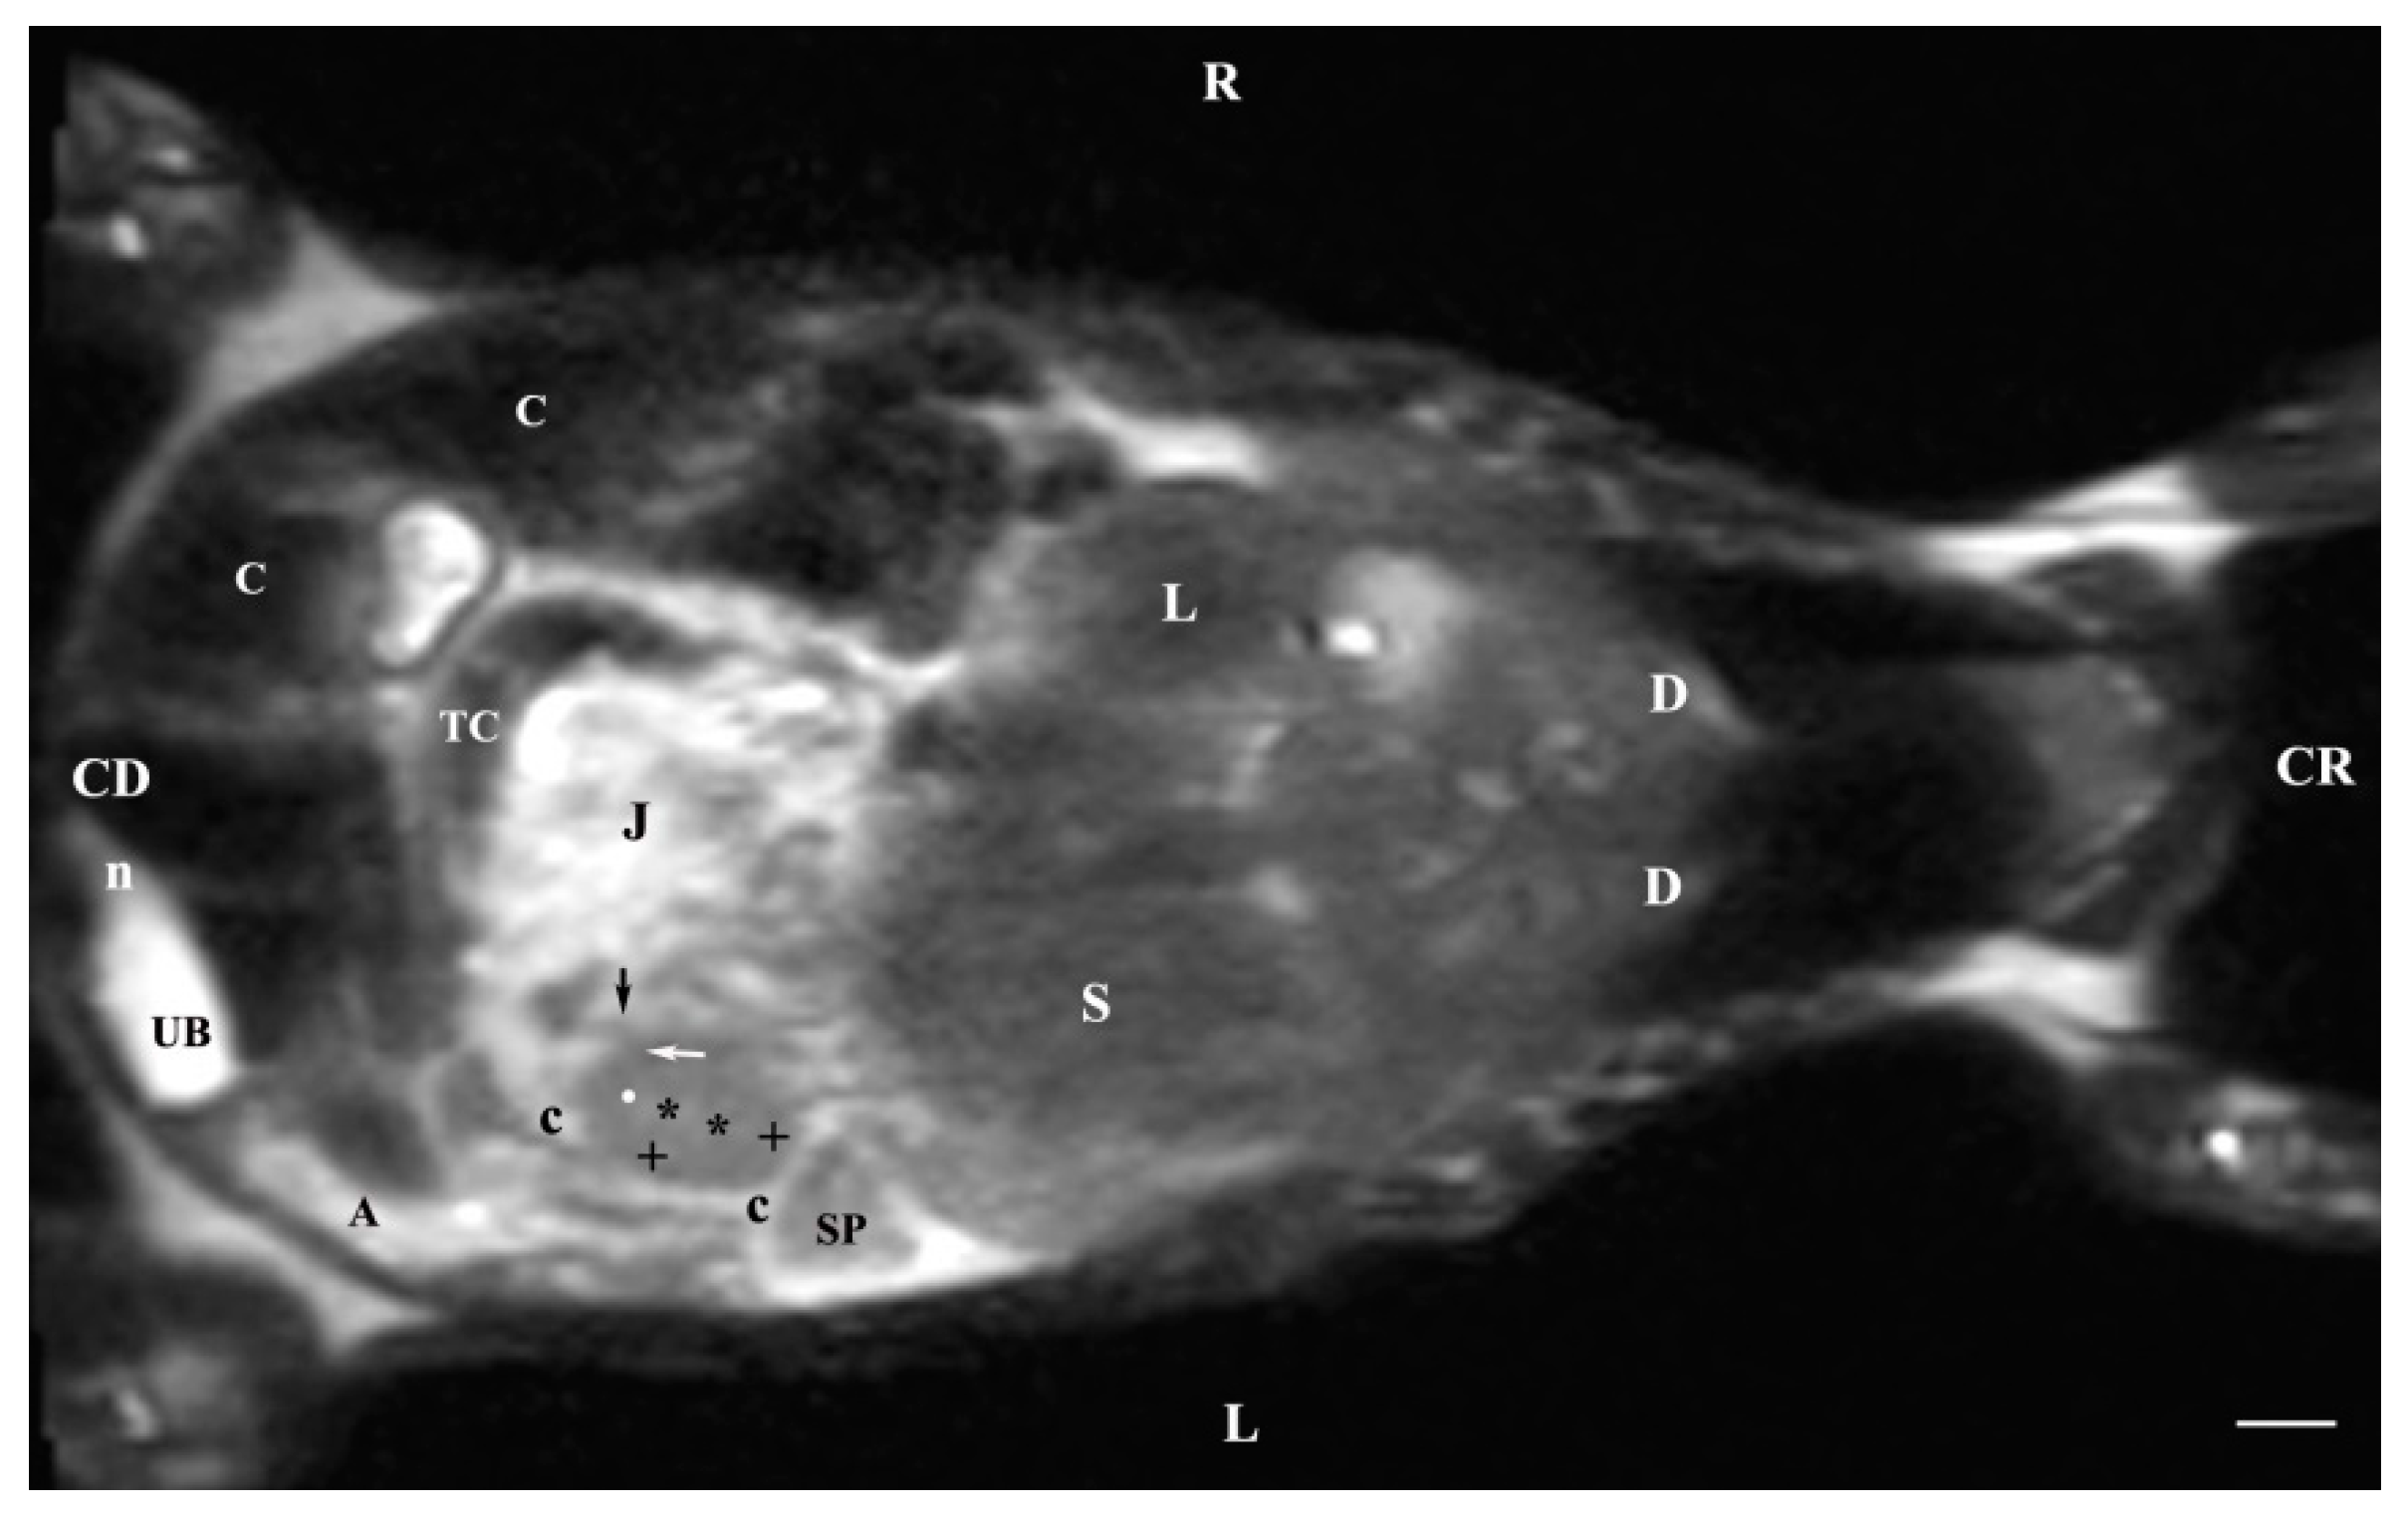

3.3. Dorsal MRI